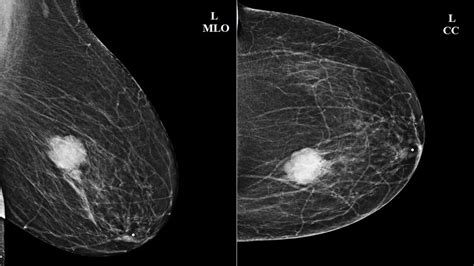

Mammography Screening or diagnostic imaging to visualize the internal structure of the breast.

• Palpable Lump: In some cases, a small lump may be felt near or directly beneath the nipple. It is usually firm and can sometimes feel movable.